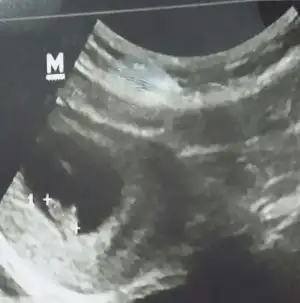

Merhabalar.. sitede yeniyim yardımlarınızı bekliyorum cinsiyet konusunda.. tam ortada sağa yığılmış ve başlangıcı solda.. karından ultrason.. teşekkür ediyorum herkese.. sağlıklı bebişler diliyorum